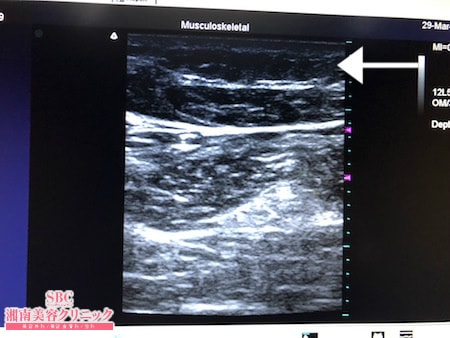

No.239881【脂肪吸引】【動画あり】湘南美容外科全ドクターの脂肪吸引最高責任者である竹田先生による脂肪吸引のフォトギャラリー!ずっとやりたいと思っていたんです!テニスで筋肉質になった太ももを少しでも細くする!術中3Dタッチビュー・右太もも後面